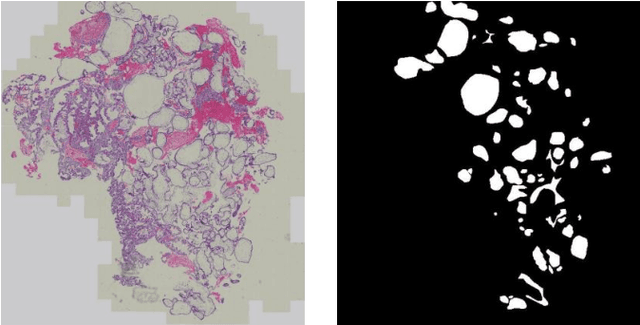

Abstract:Pathological morphology diagnosis is the standard diagnosis method of hydatidiform mole. As a disease with malignant potential, the hydatidiform mole section of hydrops lesions is an important basis for diagnosis. Due to incomplete lesion development, early hydatidiform mole is difficult to distinguish, resulting in a low accuracy of clinical diagnosis. As a remarkable machine learning technology, image semantic segmentation networks have been used in many medical image recognition tasks. We developed a hydatidiform mole hydrops lesion segmentation model based on a novel loss function and training method. The model consists of different networks that segment the section image at the pixel and lesion levels. Our compound loss function assign weights to the segmentation results of the two levels to calculate the loss. We then propose a stagewise training method to combine the advantages of various loss functions at different levels. We evaluate our method on a hydatidiform mole hydrops dataset. Experiments show that the proposed model with our loss function and training method has good recognition performance under different segmentation metrics.

Abstract:As a disease with malignant potential, hydatidiform mole (HM) is one of the most common gestational trophoblastic diseases. For pathologists, the HM section of hydrops lesions is an important basis for diagnosis. In pathology departments, the diverse microscopic manifestations of HM lesions and the limited view under the microscope mean that physicians with extensive diagnostic experience are required to prevent missed diagnosis and misdiagnosis. Feature extraction can significantly improve the accuracy and speed of the diagnostic process. As a remarkable diagnosis assisting technology, computer-aided diagnosis (CAD) has been widely used in clinical practice. We constructed a deep-learning-based CAD system to identify HM hydrops lesions in the microscopic view in real-time. The system consists of three modules; the image mosaic module and edge extension module process the image to improve the outcome of the hydrops lesion recognition module, which adopts a semantic segmentation network, our novel compound loss function, and a stepwise training function in order to achieve the best performance in identifying hydrops lesions. We evaluated our system using an HM hydrops dataset. Experiments show that our system is able to respond in real-time and correctly display the entire microscopic view with accurately labeled HM hydrops lesions.